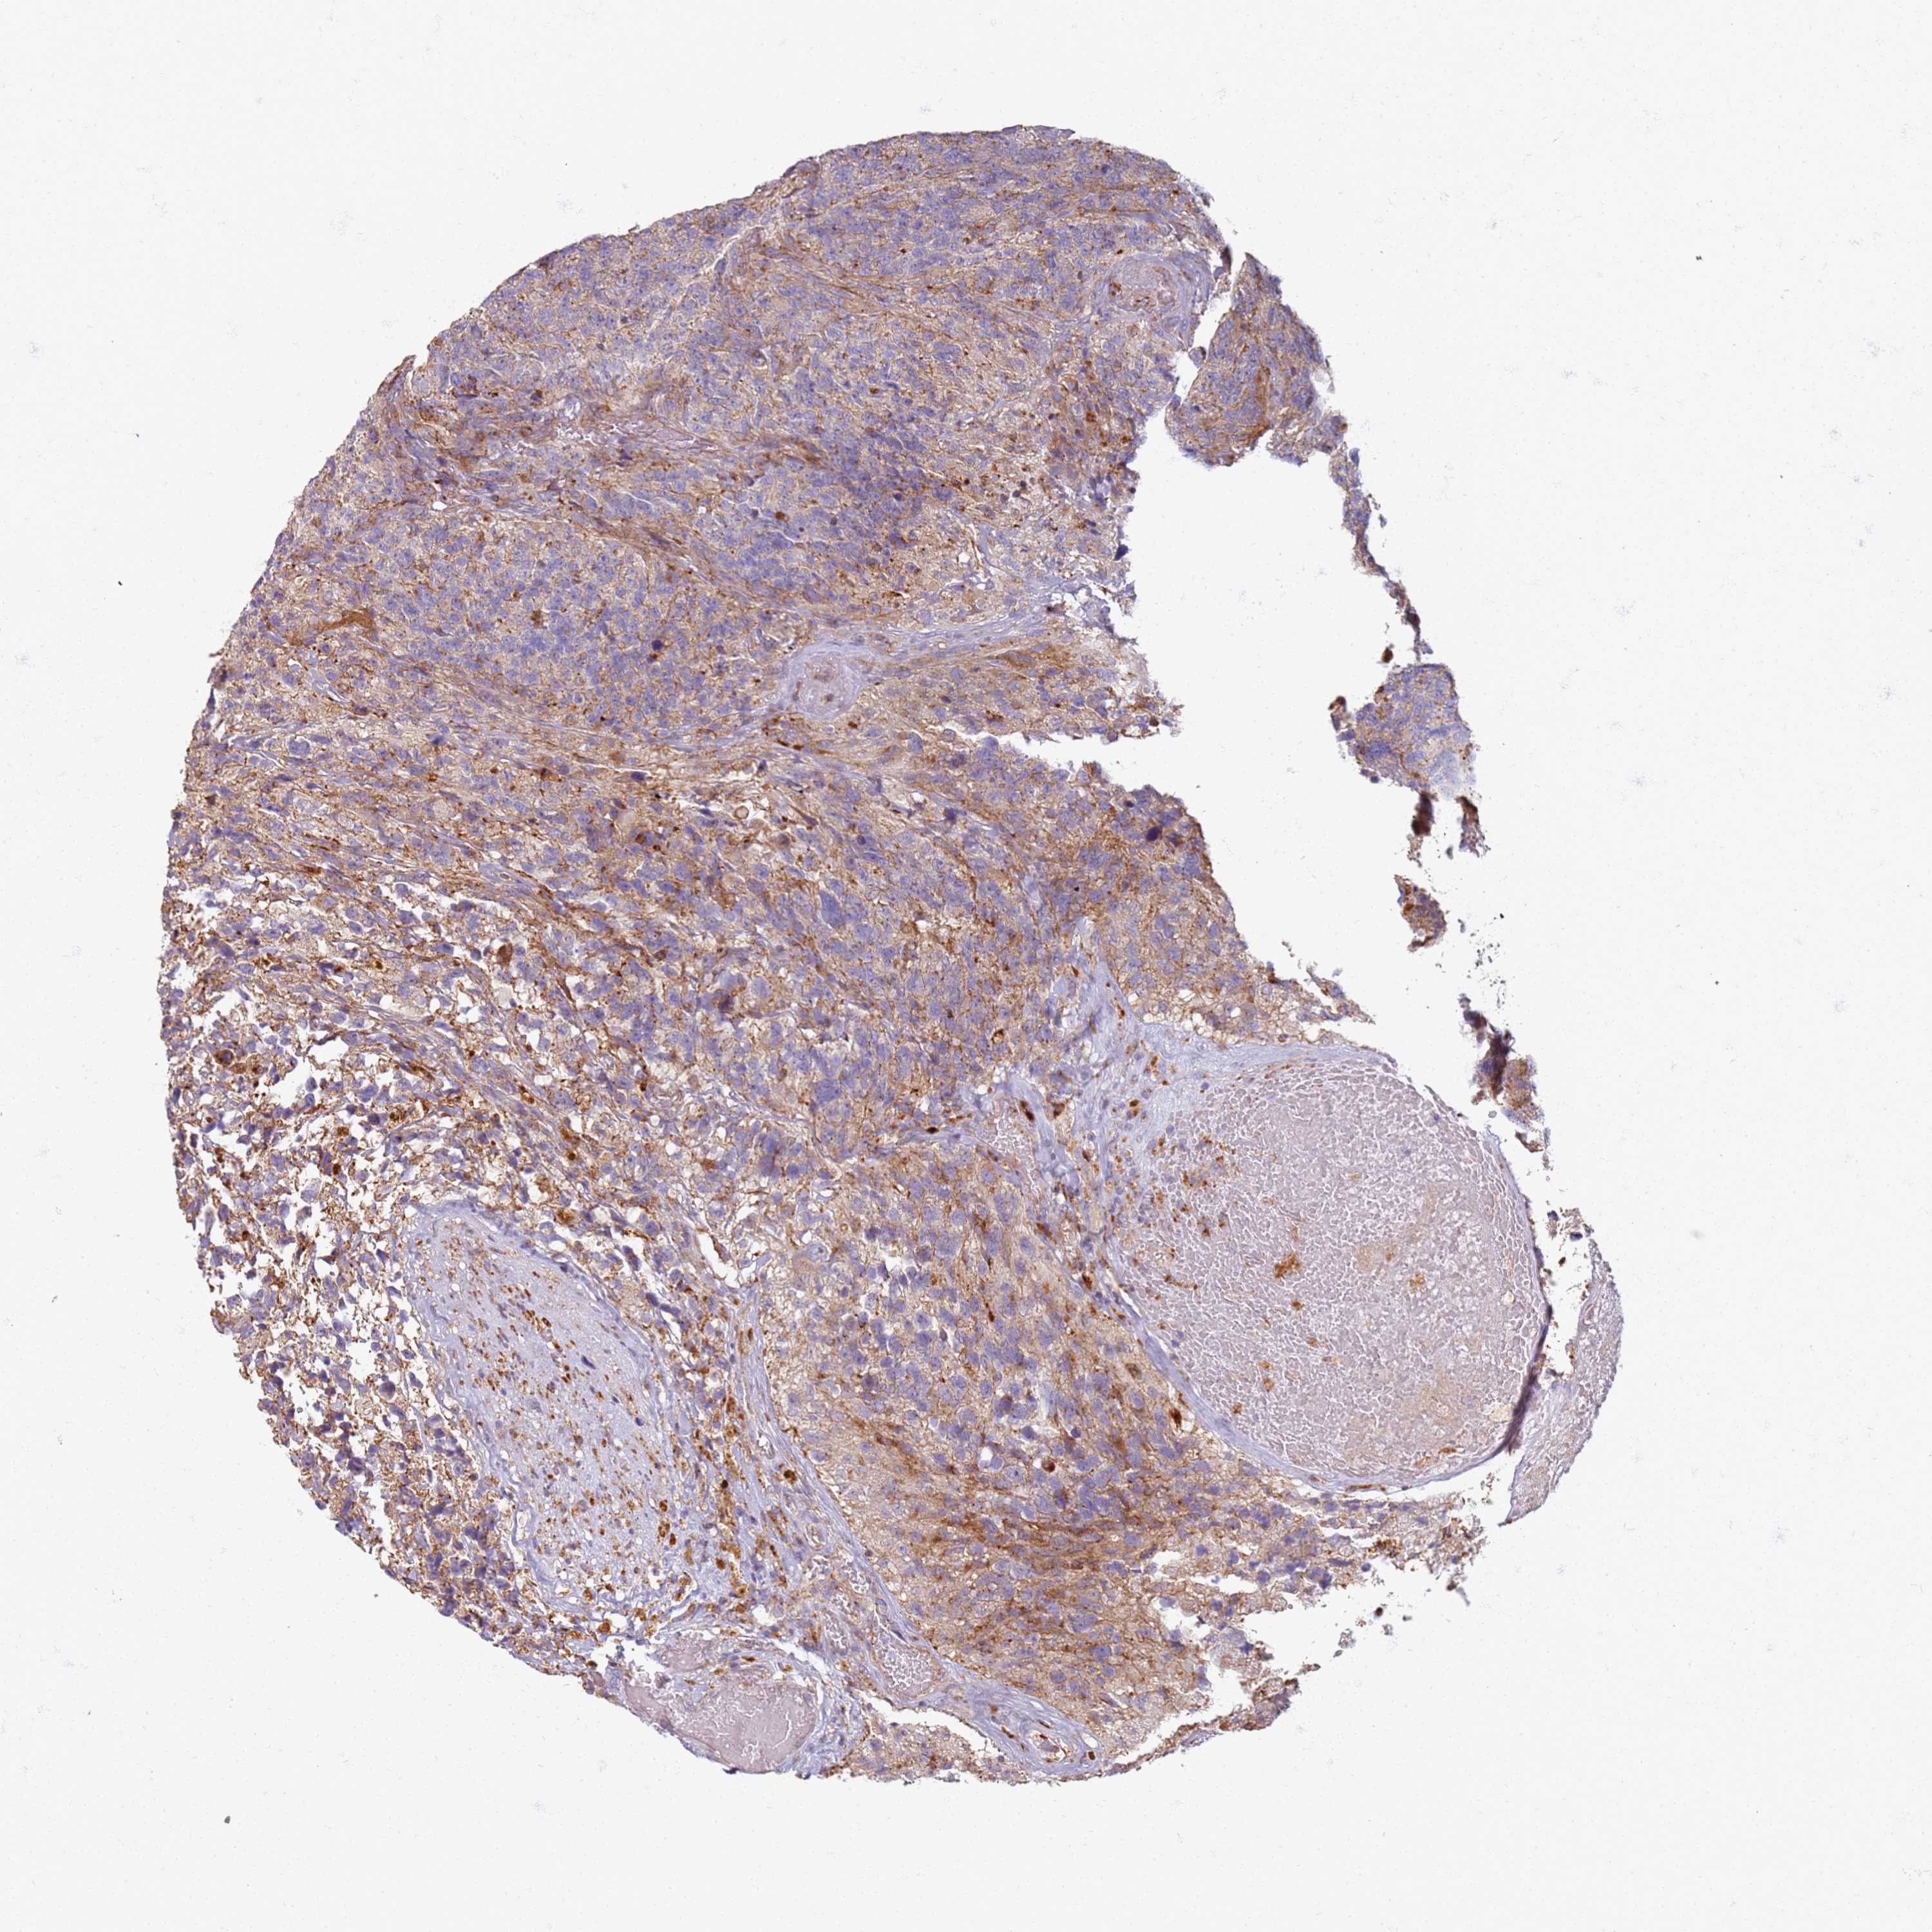

GLIOMA - Protein expressioni

A mouse-over function shows sample information and annotation data. Click on an image to view it in a full screen mode. Samples can be filtered based on level of antibody staining by selecting one or several of the following categories: high, medium, low and not detected. The assay and annotation is described here.

Note that samples used for immunohistochemistry by the Human Protein Atlas do not correspond to samples in the TCGA dataset.

Antibody stainingi

Antibody staining in the annotated cell types in the current human tissue is reported as not detected, low, medium, or high, based on conventional immunohistochemistry profiling in selected tissues. This score is based on the combination of the staining intensity and fraction of stained cells.

Each image is clickable and will lead to virtual microscopy that enables deeper exploration of all samples and also displays staining intensity scores, fraction scores and subcellular localization as well as patient and tissue information for each sample.

Antibody HPA047281

Staining

High

Medium

Low

Not detected

Intensity

Strong

Moderate

Weak

Negative

Quantity

>75%

75%-25%

<25%

None

Location

Nuclear

Cytoplasmic/membranous

Cytoplasmic/membranous,nuclear

Glioma, malignant, Low grade

Glioma, malignant, High grade

Glioblastoma, NOS